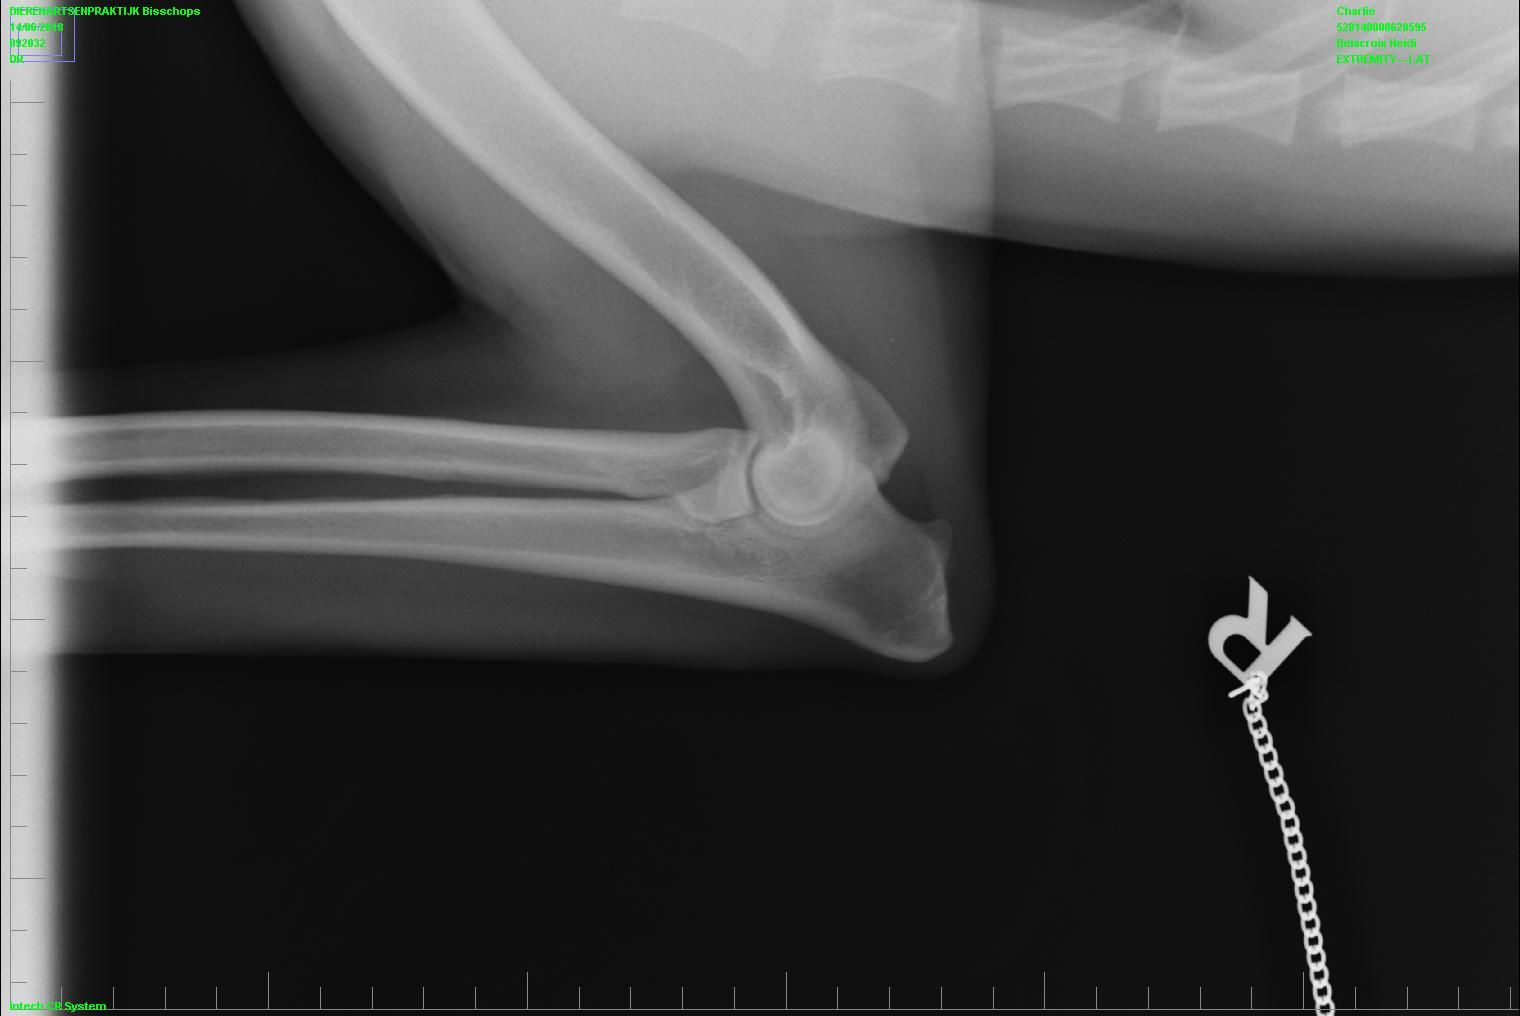

• heupen (kwalificatie A , Norberg L106 R103)

• ellebogen (kwalificatie 0 )